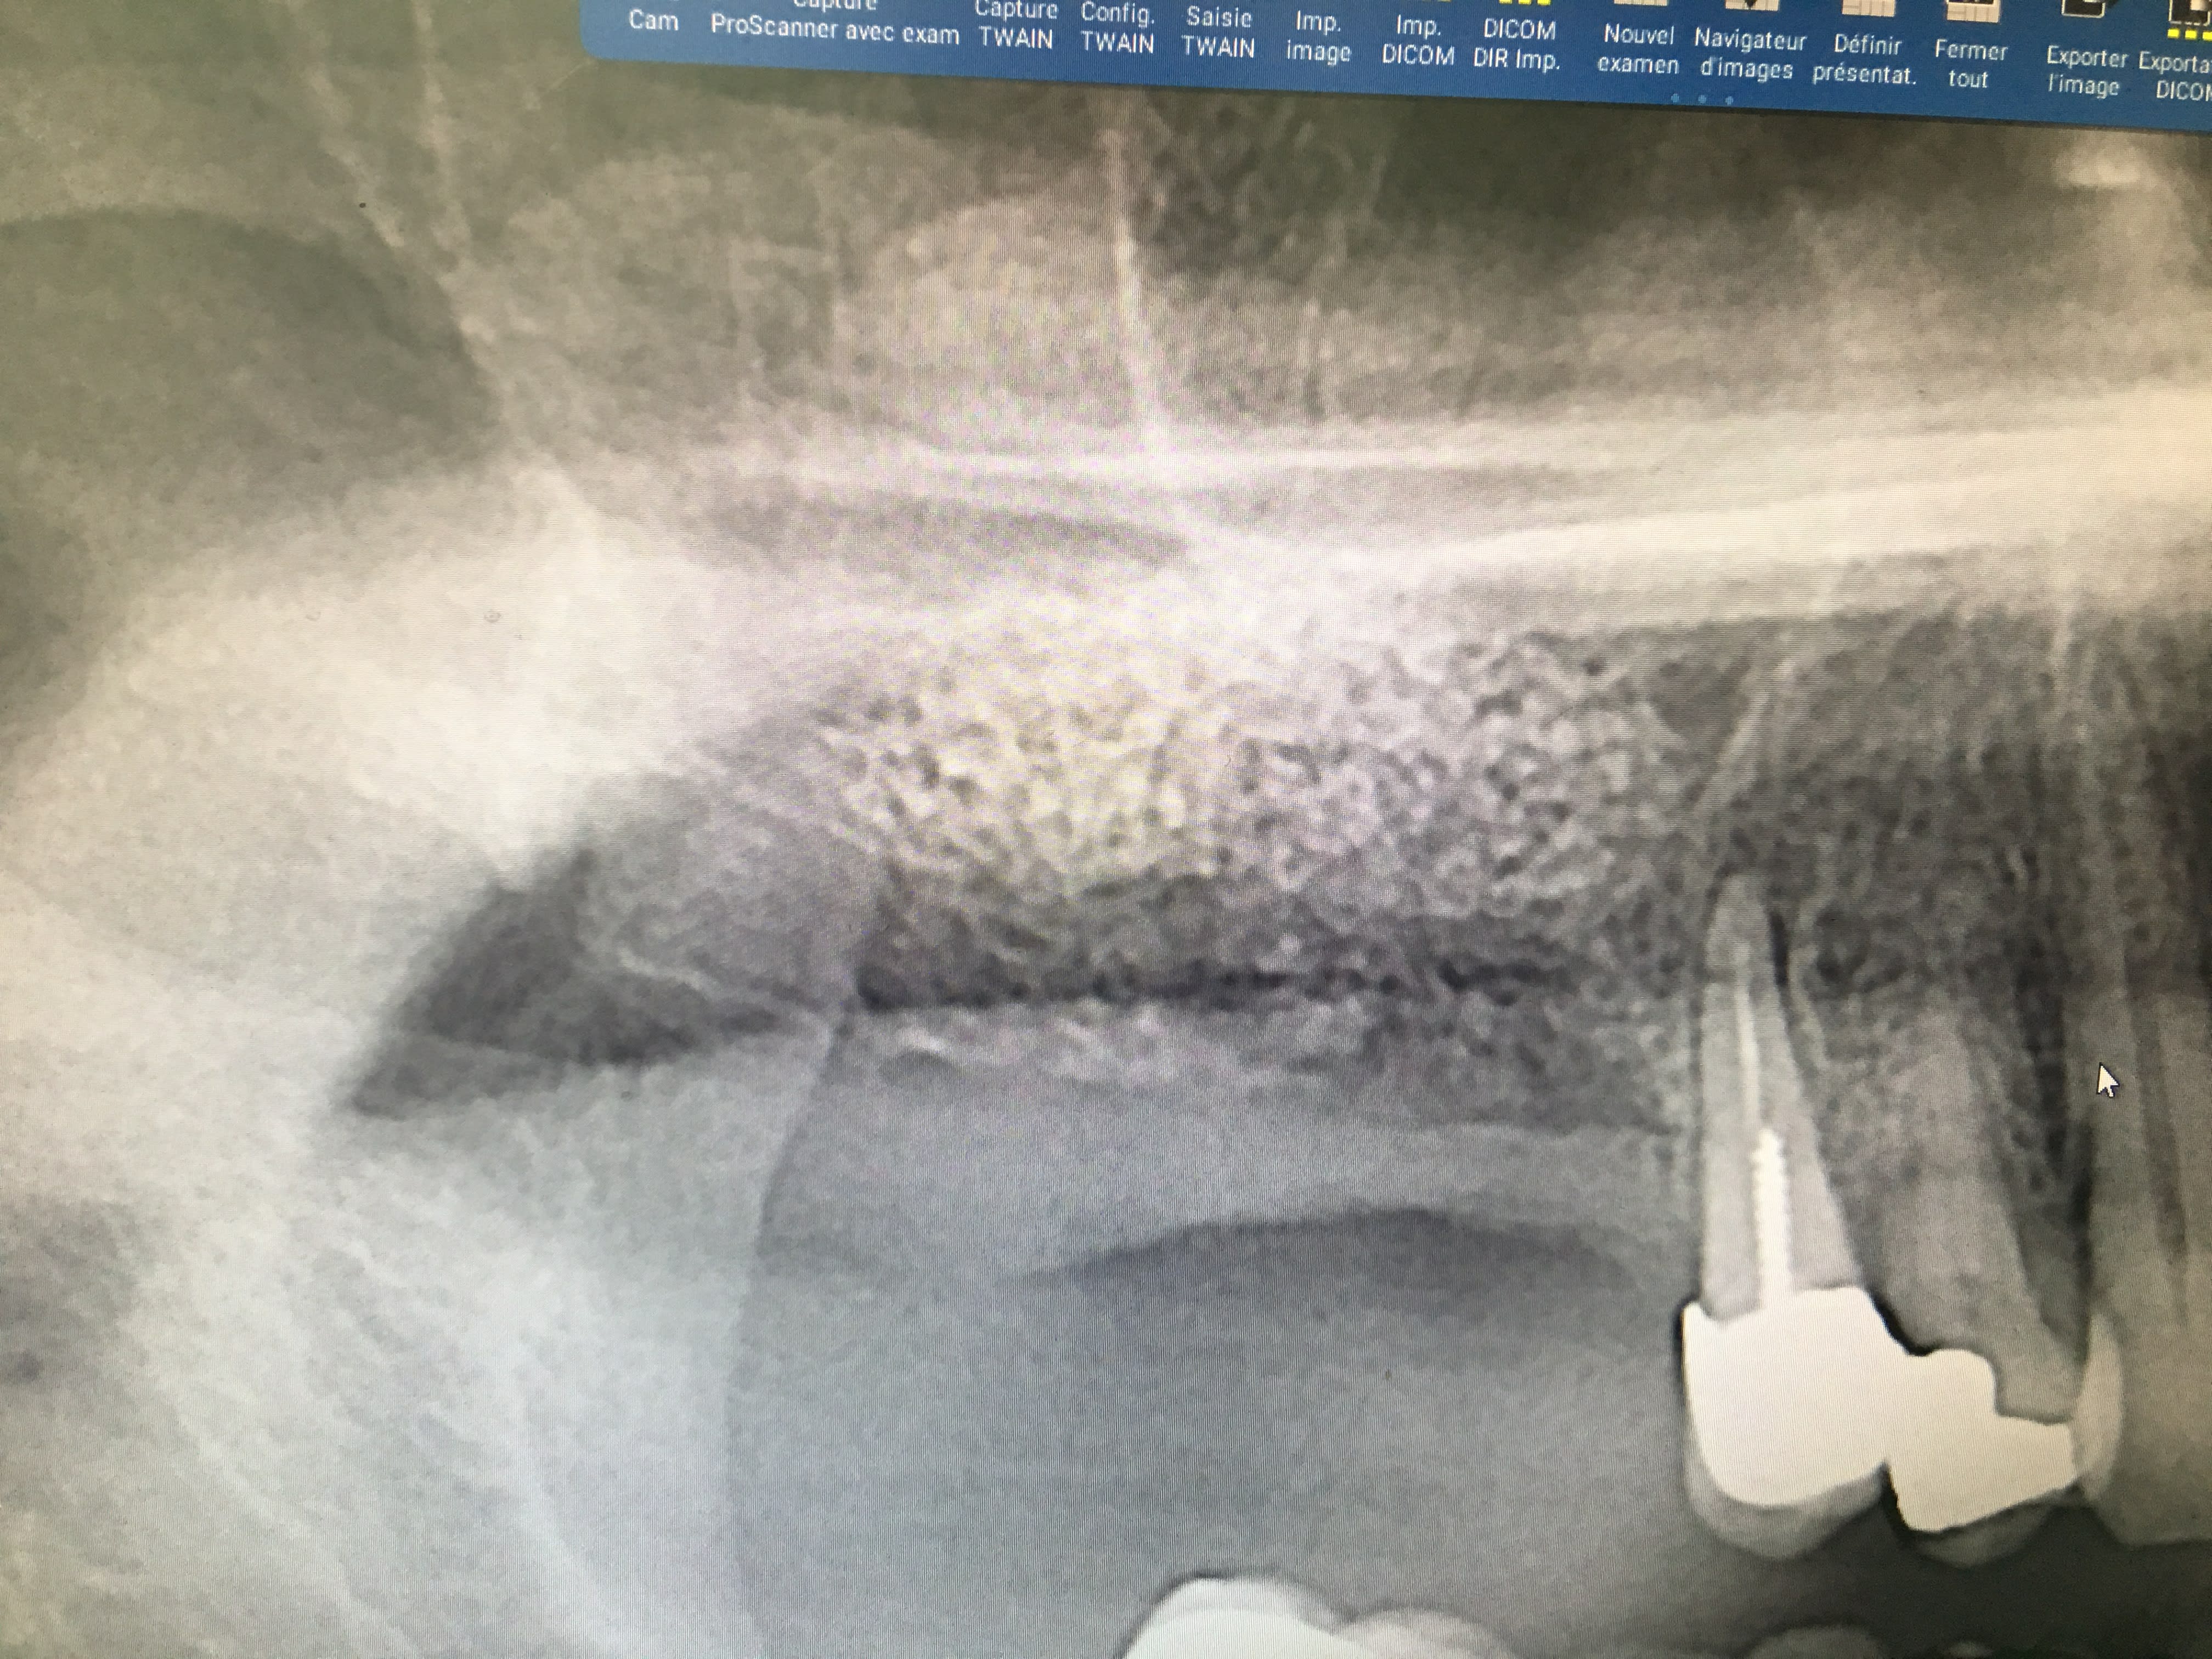

Aie aie aie il va falloir investir dans un cone-beam pour les contrôles post OP, la pano bof bof.

Je fait des panos pour des raisons de ALARA meme si avec les conebeams aujourdui le dose est reduit. (BTW, les images sont des photos d'un ecran donc pas super qualité). Par contre si les autres ont l'habitudes to fair des scans de control, je les suivre.

Non, ca ne m'inquieterais pas, parfois la membrane ne bouge pas (plus epaisse, patient ne respire pas fort, pas le bon jour...), a ce moment j'essaie de verifier son integrite visuellement. En tout cas vu la radio du premier cas aucune inquietude, on voit bien un volume defini, c'est donc qu'il n'y a pas de dechirure. Sur la deuxieme, la qualite est trop mauvaise, franchement je ne vois rien.